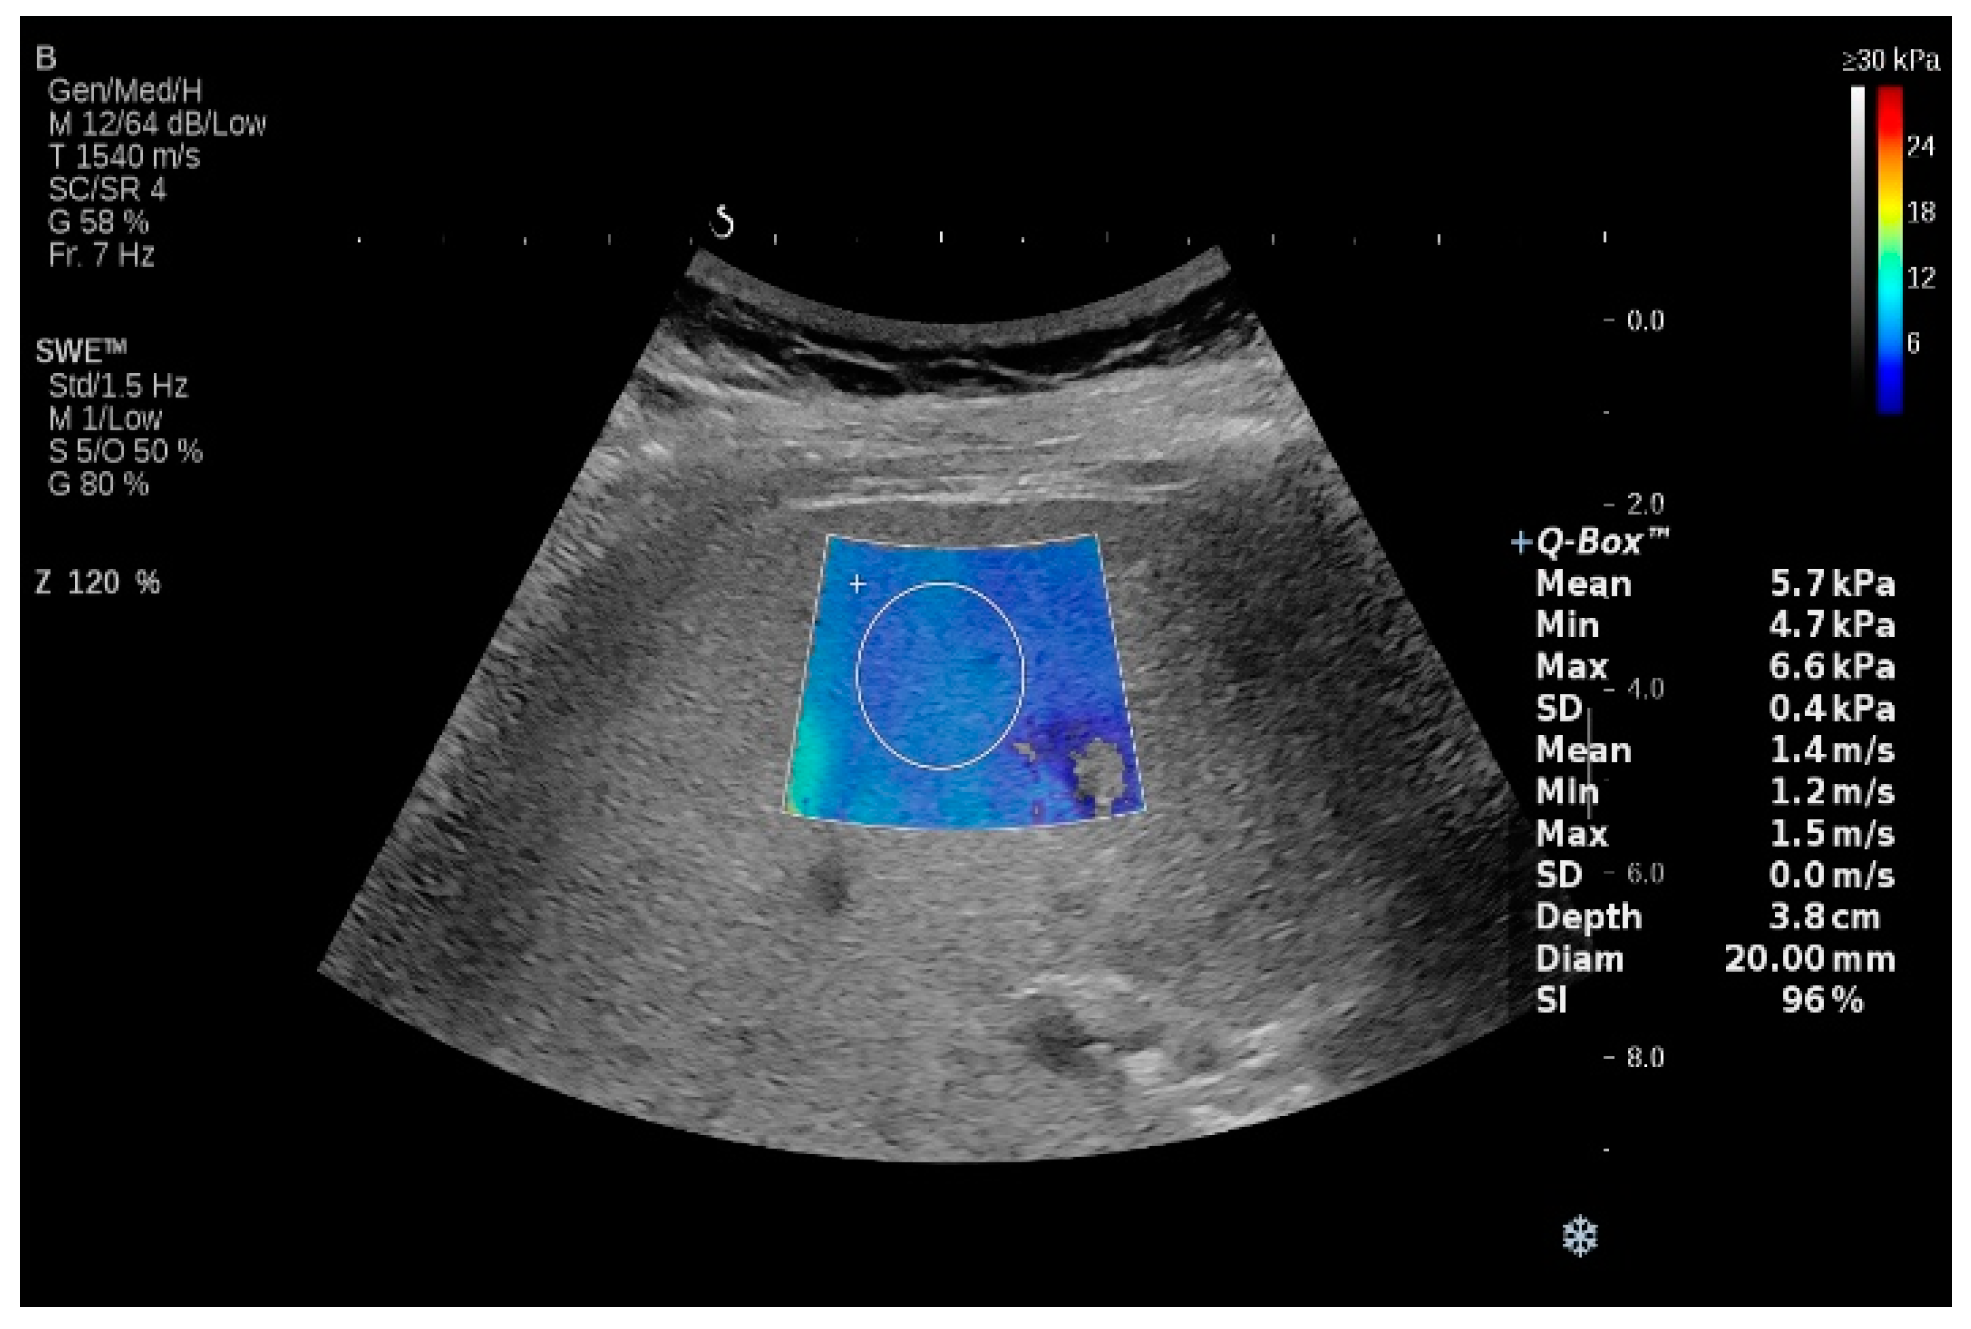

2.3. Two-Dimensional Shear Wave Elastography (2D-SWE)

2.3.1. Performance of 2D-SWE for Liver Fibrosis Assessment in NAFLD and NASH

2.3.2. Evaluation of Hepatic Steatosis in NAFLD and NASH Using 2D-SWE Techniques